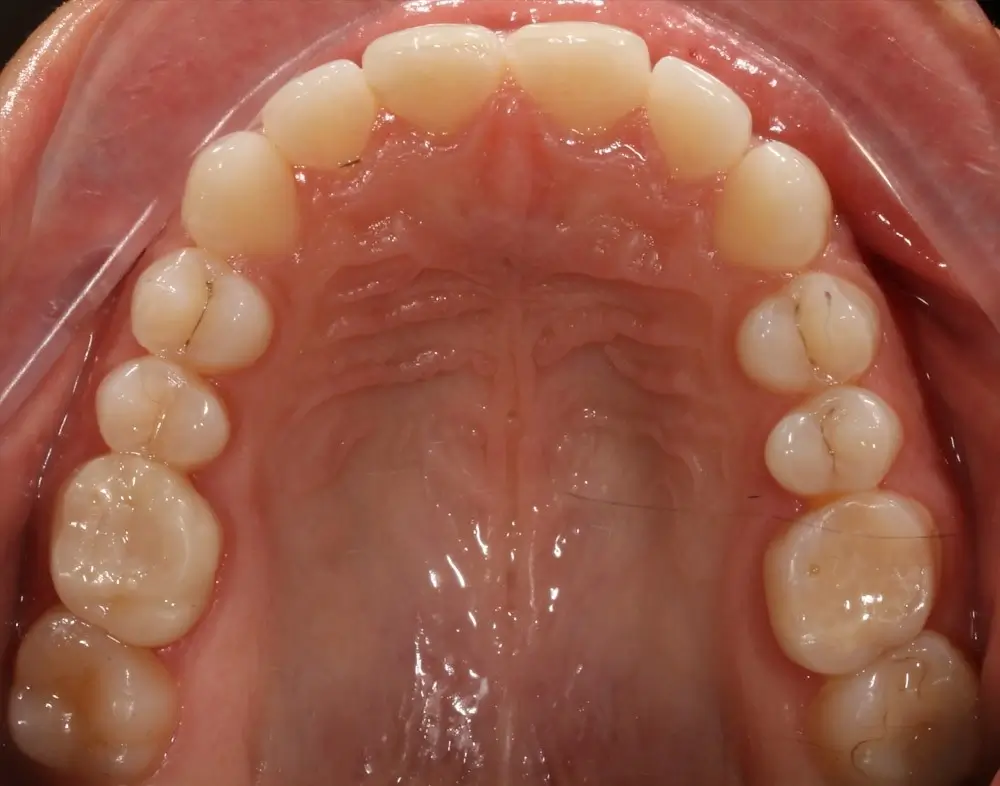

Открытый прикус - Кейс 4

Эффективность устранения дефекта прикуса посредством элайнеров FlexiLigner.

Результаты лечения